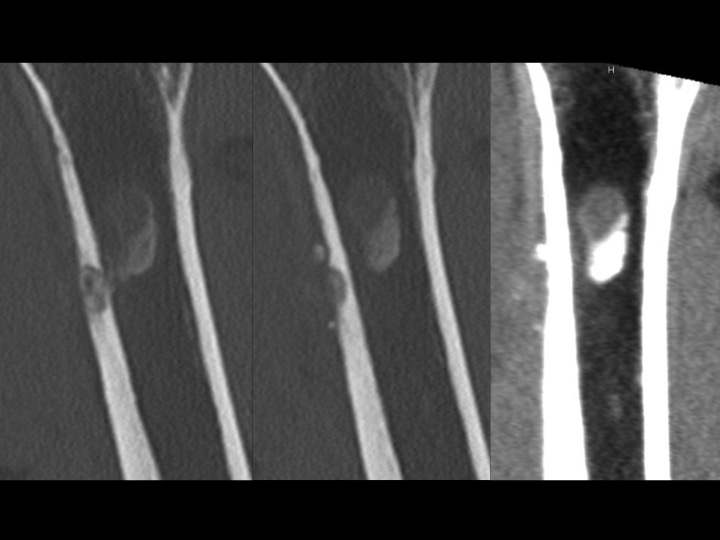

Fell 2 months earlier with minor persistent symptoms, acutely worse x 3 days opening a door. He reported night pain and pain with reaching. 80% improved after 2 days on Medrol dose pak. MRI shows subcortical humeral shaft marrow and parosteal edema with dark signal foci in the region of the pectoralis major insertion. CT shows both peri-tendinous calcifications as well has HADD deposits eroding through the cortex and into bone. Axillary XR clearly shows the peri-tendinous deposit; the cortical erosion is faintly visible....and I expect you can all see the intra-osseous calcific deposit.

tendon of pectoralis major ( RID2007 )